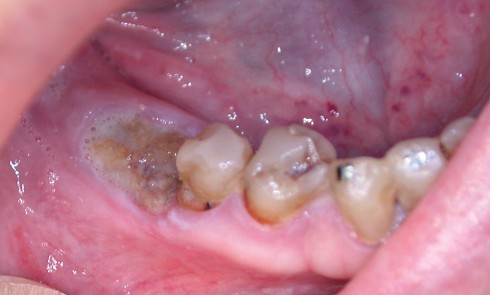

Article réservé à nos abonnés Comment traiter les ostéonécroses des mâchoires ? Traitement médical ou chirurgical ?

En 2014, l’American Association of Oral and Maxillofacial Surgeons (AAOMS) [1] a défini les critères de diagnostic de l’ostéonécrose (tableau 1), les...